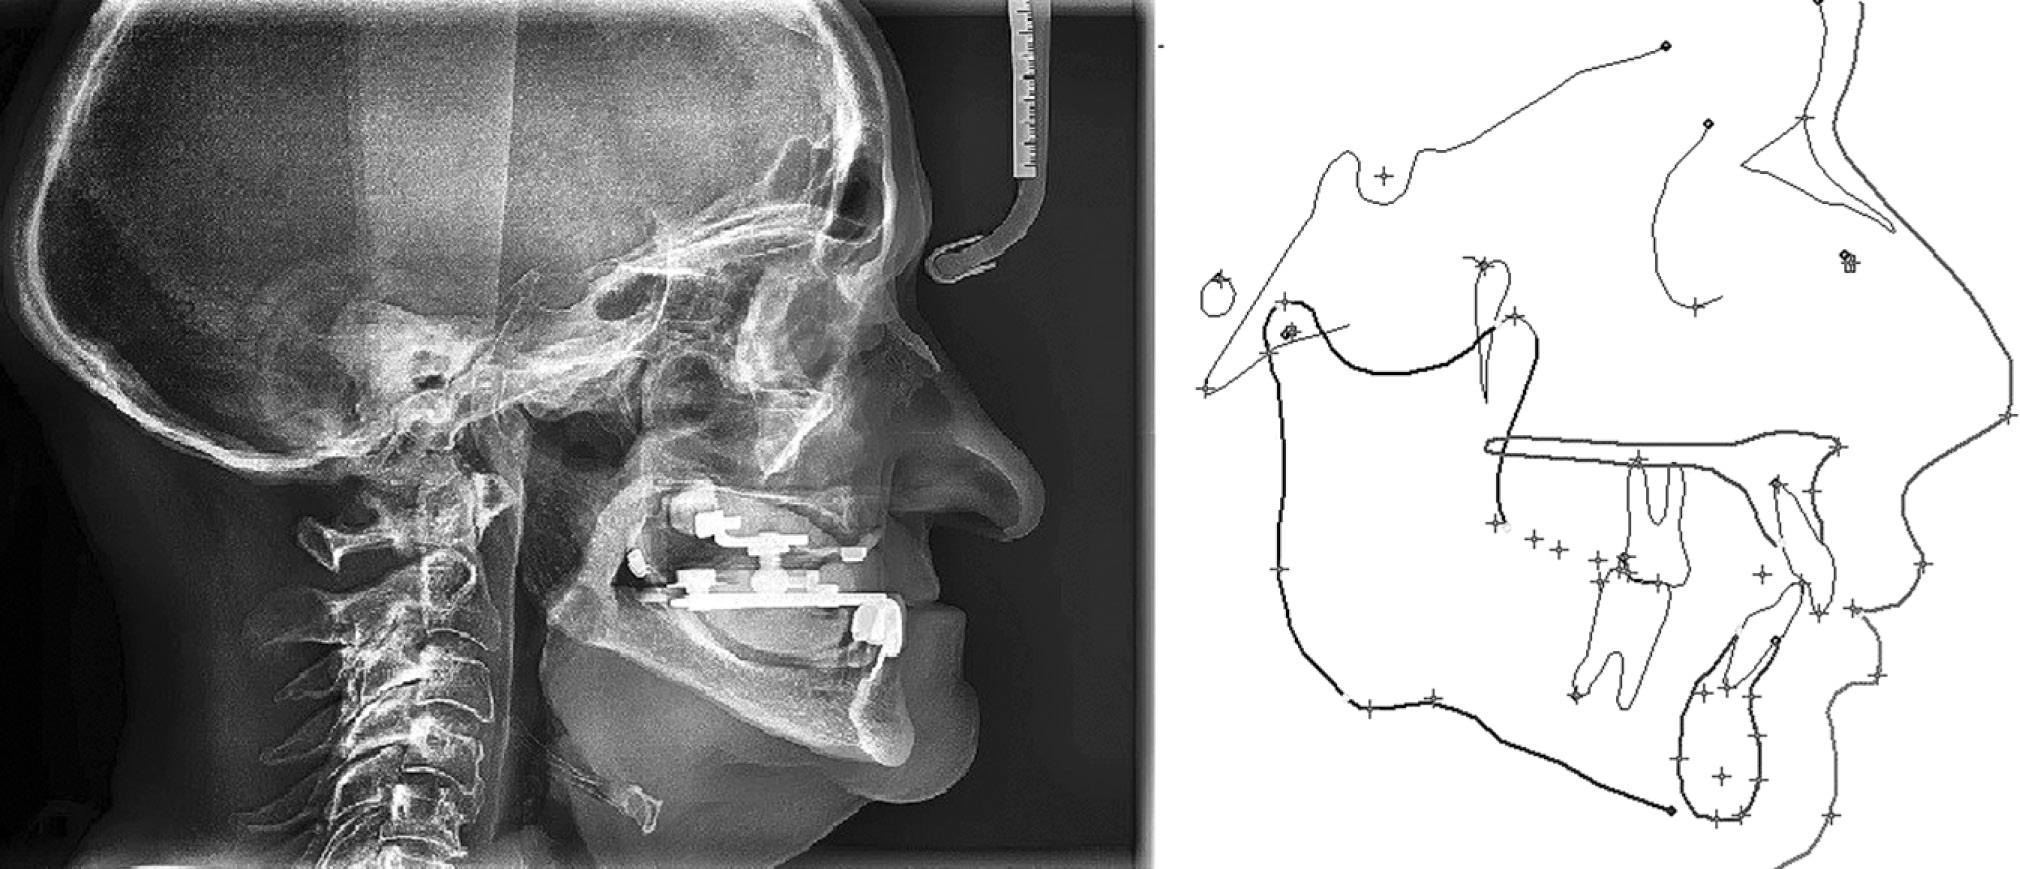

Поскольку автор [25] при создании концепции объяснял наличие верхней и нижней границы значения возрастным истиранием зубов и уменьшением длины канала для возрастных больных, мы используем данное значение по нижней границе, т. е. 15 мм. На этом этапе очень важно соблюсти наклон протетической плоскости, иначе шар в соответствии с феноменом Христенсена [26] будет отрываться от плиты во время функциональных движений. После установки элементов гнатометра на жесткий базис согласно этим ориентирам собранный гнатометр передают в клинику для определения ЦСЧ. В клинике после установки гнатометра в полость рта определяют высоту прикуса методом вычета 2 мм от высоты физиологического покоя. Далее после фиксации высоты прикуса посредством контргайки на верхней челюсти на нижнюю плиту наносят перманентный маркер (также для этих целей можно использовать окклюзионный спрей), после чего гнатометр помещают в полость рта и пациента просят выполнить функциональные нижнечелюстные движения: 1) вперед — назад (протрузия — ретрузия); 2) влево — в центр (латеротрузия левая — ЦСЧ); 3) вправо — в центр (латеротрузия правая — ЦСЧ); 4) влево — вправо (латеротрузия левая — латеротрузия правая). После данной манипуляции гнатометр извлекают из полости рта для анализа полученного графика. Точка пересечения всех линий — ЦСЧ, однако не стоит спешить фиксировать ее — для контроля необходимо провести повторное исследование, перед которым нужно закрасить все помехи маркером и отметить точку найденного центра при первичном исследовании. В случае если центр, полученный после второго исследования, совпадет с первым, ЦСЧ определено правильно, и его необходимо зафиксировать. Перед тем как зафиксировать ЦСЧ, необходимо установить зажим на расстоянии 5–8 мм (в зависимости от длины протрузионной линейки артикулятора) по графику протрузионной дорожки для записи данных угла сагиттального суставного пути в соответствии с феноменом Христенсена. После этого гнатометр помещают в полость рта, и положение протрузии фиксируют силиконовым регистратом из лабораторного силикона. Далее гнатометр снова извлекают из полости рта, разъединяют и извлекают протрузионный регистрат, после чего для фиксации найденного положения применяют зажим, позволяющий зафиксировать шар под разными углами посредством винта. Отверстие в зажиме позволяет точно прицелиться в точку ЦСЧ на графике для установки зажима, дополнительно для надежной транспортировки гнатометр во рту связывают лабораторным силиконом. Во время выполнения ТРГ-исследования гнатометр помещают в полость рта, после чего выполняют анализ полученного снимка (рис. 4).

Рис. 4. Снимок телерентгенограммы и его анализ.

Fig. 4. A snapshot of the telerentgenogram and its analysis.

Поскольку цефалометрия столь тесно связана с прогнозированием роста у детей, она не получает должного внимания в качестве средства, помогающего планировать ортопедическое лечение у взрослых. Кроме того, сложность анализа роста приводит к ненужным и затрудненным попыткам упростить цефалометрию для применения общими стоматологами и стоматологами, специализирующимися на реставрации. Однако метод обладает большой ценностью в анализе проблем окклюзии, а поскольку анализ роста необязателен для зрелых пациентов, применение цефалометрии может быть упрощено. Абсолютная приверженность цефалометрическим нормам не обеспечивает достаточной информации для принятия окончательного лечебного решения [27]. Ее применение должно сочетаться с анализом факторов, актуальных для беззубых челюстей, для принятия окончательного лечебного решения. Для стоматологов-ортопедов цефалометрия представляет особый интерес, так как по сути является рентгеновским снимком в сагиттальной проекции с лицевой дугой. Именно наличие двух ушных упоров и носового упора, как у лицевой дуги, и послужило причиной большого интереса со стороны врачей — стоматологов-ортопедов к снимкам ТРГ. В первую очередь необходимо определить скелетный класс. Это можно произвести множеством способов. Наиболее простым и удобным для проведения в клинике являются анализ по Witz и определение параметров, характеризующих вертикальные размеры лица: N – me (PN), т. е. передняя высота лица измеряется как проекционное расстояние по носовой плоскости между точками N и me. У мужчин этот показатель в норме составляет 124,38±3,62 мм, у женщин 112,46±3,17 мм [28]. В нашем случае он составлял 125 мм, т. е. вертикальный размер лица соответствует норме, следовательно, высота окклюзии в момент определения ЦСЧ не была завышена или занижена. Далее данные анализа цефалометрии, лицевой дуги, гнатометр и гипсовые модели челюстей передают в лабораторию для выполнения постановки зубов.